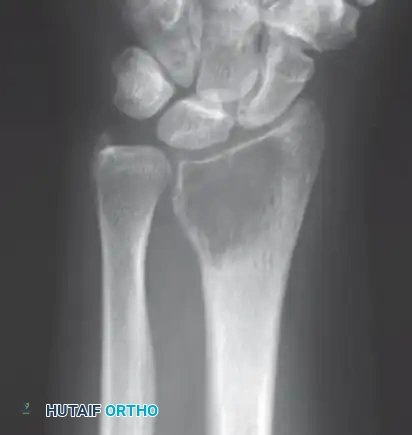

Intraoperative Imaging and Margin Assessment

Continuous intraoperative assessment using fluoroscopy and frozen section pathology is mandatory. The following images demonstrate various stages of complex upper extremity resections, allograft preparations, and prosthetic implantations across the humerus and elbow joint.